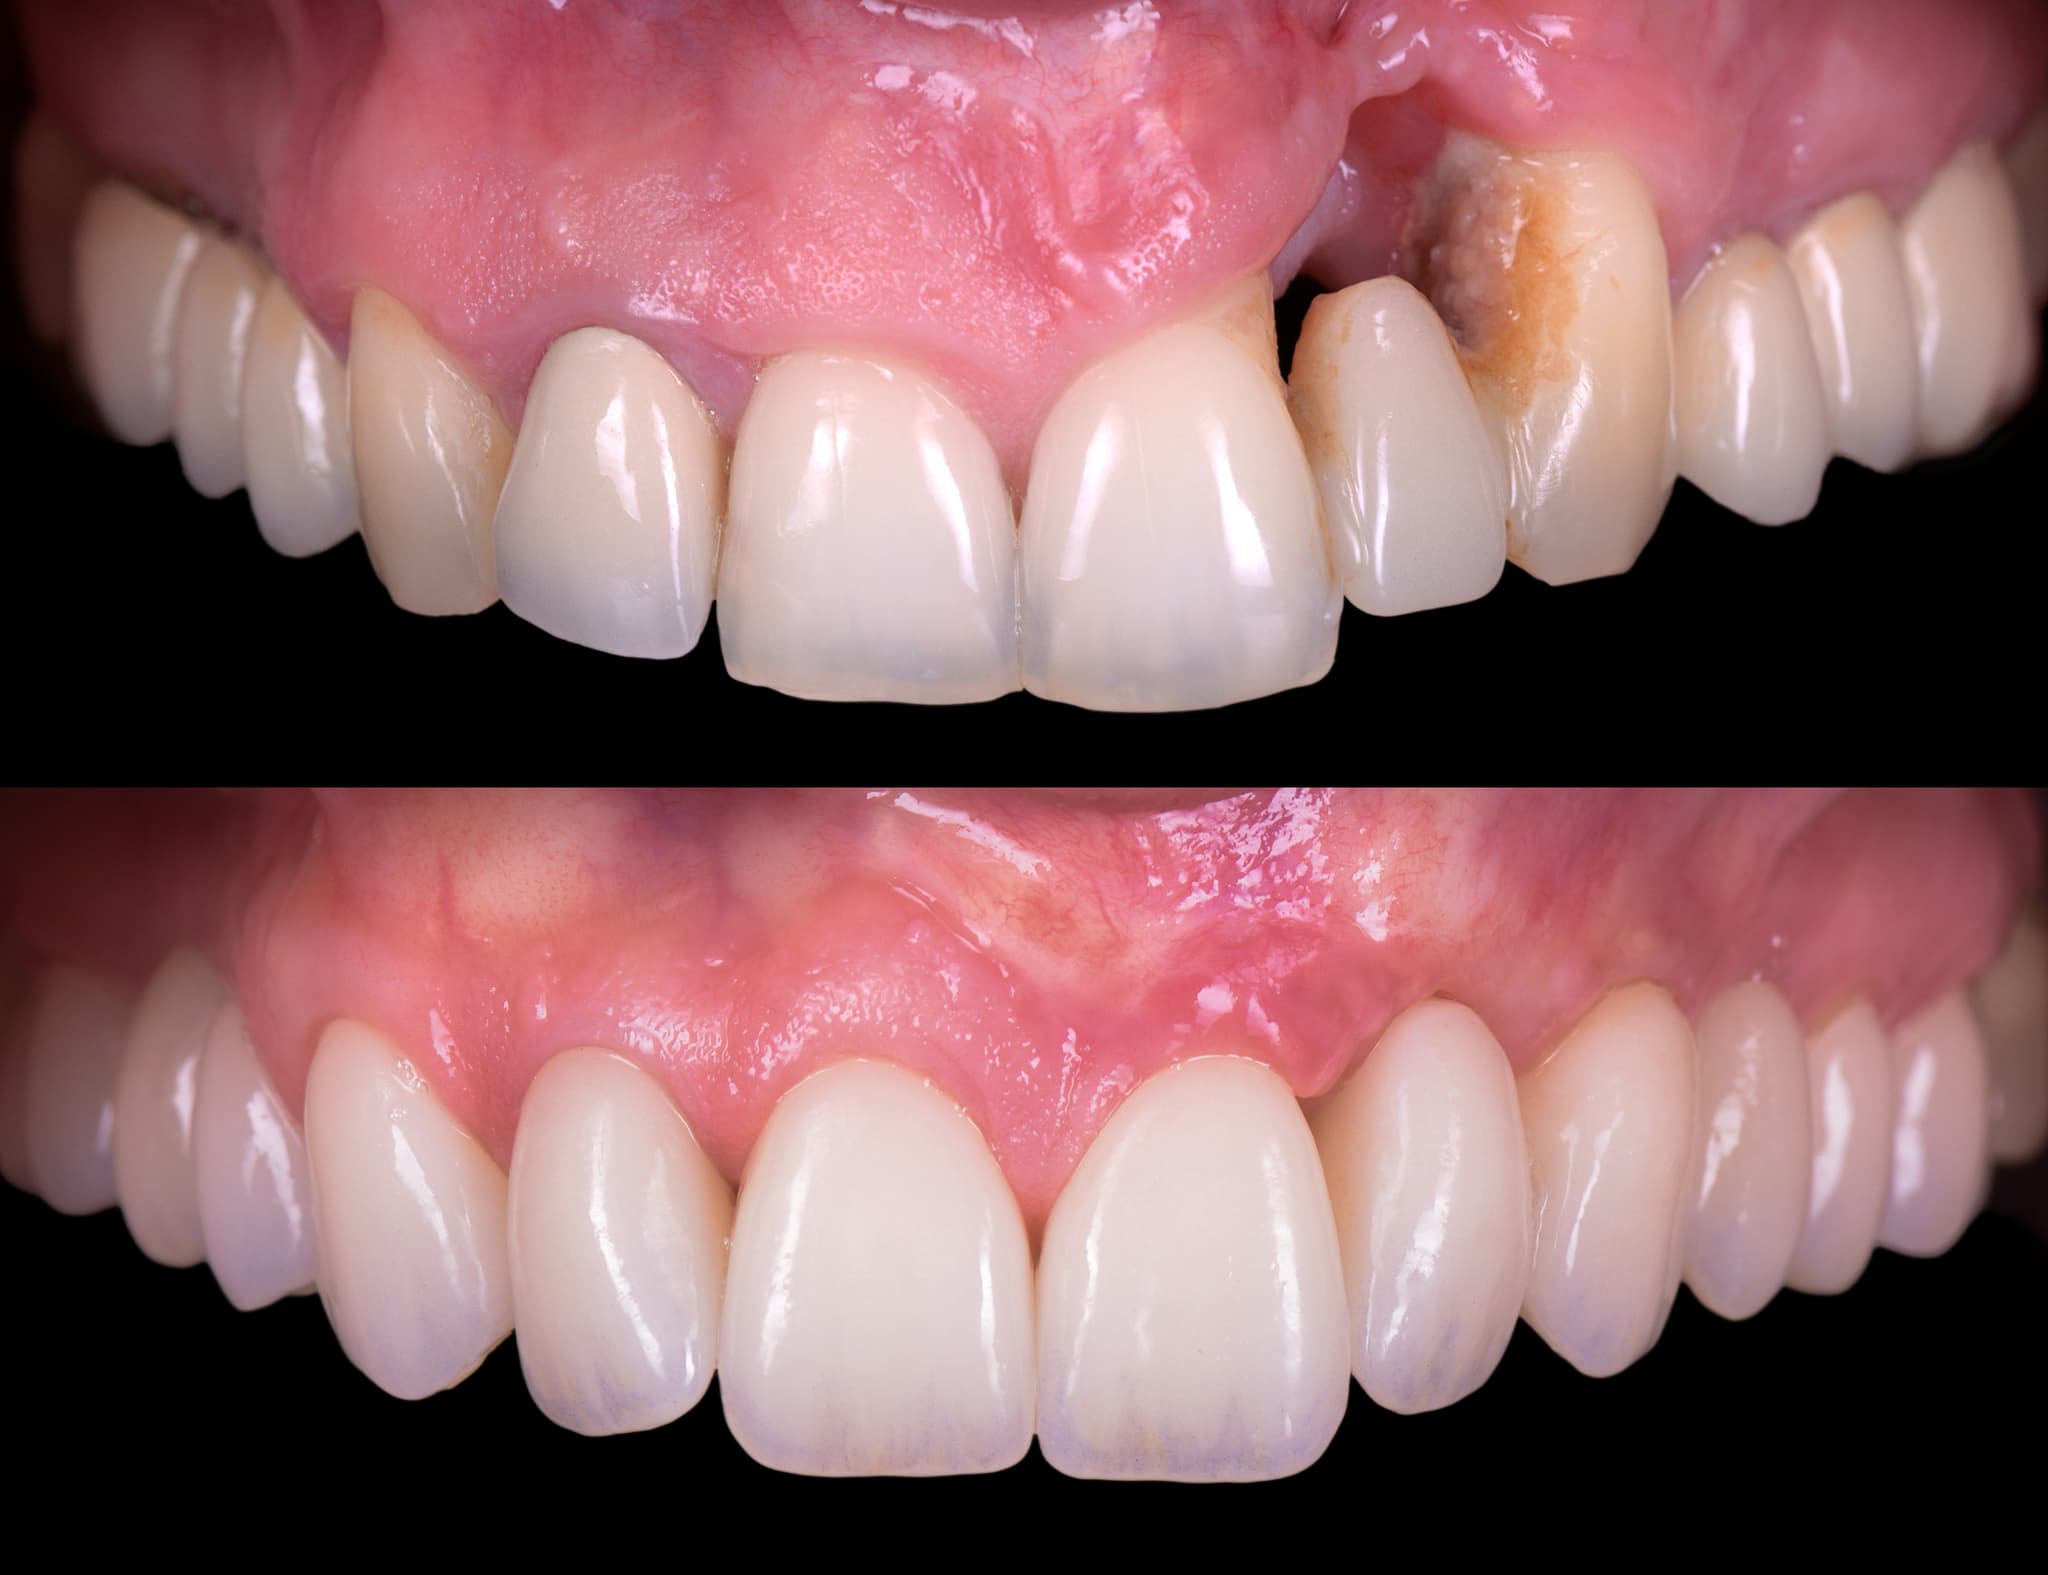

În cazurile cu pierdere osoasă sau retracție gingivală, evaluăm posibilitatea regenerării. Folosind biomateriale și principii de vindecare ghidată, reconstruim suportul în zonele selectate. Atunci când este luată în calcul inserarea de implanturi, regenerarea ajută la crearea unei baze stabile. Obiectivul nostru nu este doar oprirea bolii—ci și refacerea arhitecturii pierdute.

Rezultatele estetice nu depind doar de ceramică—ci și de sănătatea și conturul țesuturilor moi. De aceea, luăm în considerare arhitectura parodontală încă din faza de design. Modelăm, protejăm și menținem țesuturile moi pentru a susține atât sănătatea, cât și armonia.